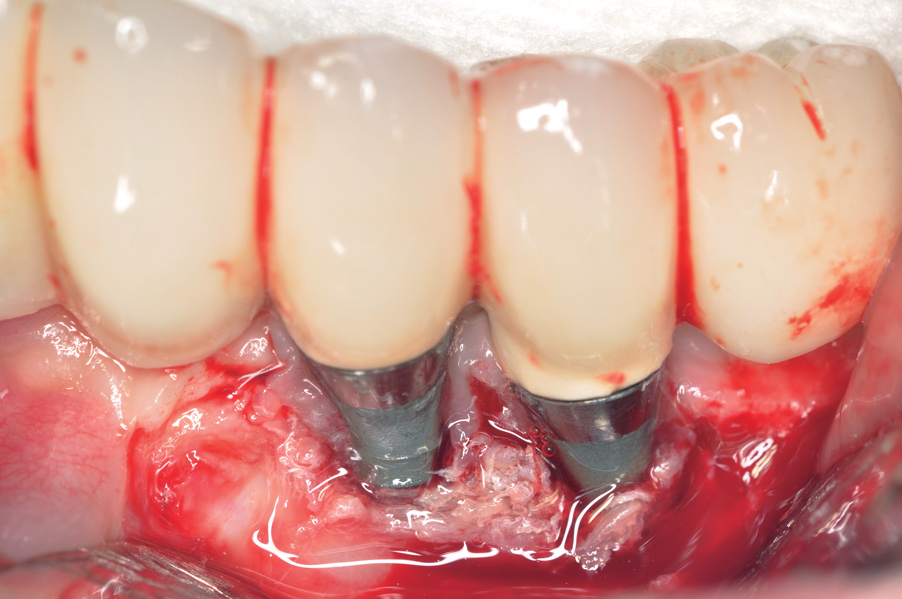

Dental implants have revolutionized the way in which clinicians treat and restore partially and fully edentulous patients and have demonstrated success for managing a broad range of clinical dilemmas. While implants have been highly predictable and have achieved long-term success, they are not immune from complications associated with improper treatment planning, poor surgical and prosthetic execution, material failure, and inadequate or infrequent maintenance. Among these problems are the biologic complications of peri-implant mucositis and peri-implantitis, which are inflammatory conditions in the soft and/or hard tissues surrounding dental implants (Figure 1 through Figure 4).1,2